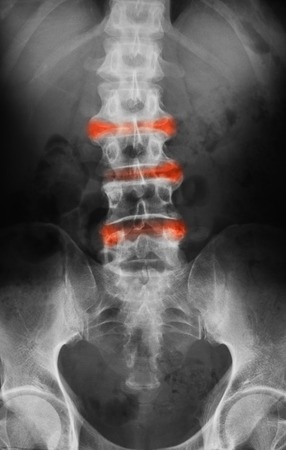

Ocena ruchomości kręgosłupa i rozszerzalności klatki piersiowej stanowią jedne z podstawowych narzędzi służących ocenie progresji zmian osiowych w przebiegu zesztywniającego zapalenia stawów kręgosłupa (ZZSK).

Wyniki analizy oceniającej zmiany w zakresie parametrów oceny ruchomości kręgosłupa wykazują, że najczęściej obserwowanymi nieprawidłowościami są (w kolejności malejącej częstości występowania): zgięcie boczne kręgosłupa - LSF (ang. lateral spinal flexion, ograniczenie ruchomości odcinka lędźwiowego kręgosłupa w płaszczyźnie czołowej), zmodyfikowany test Schobera, odległość tragus – ściana, rotacja odcinka szyjnego kręgosłupa, odległość międzykostkowa i rozszerzalność klatki piersiowej. Obserwowana kolejność zmian była stała na przestrzeni czasu i niezależna od płci, czasu trwania objawów oraz obecności zmian radiologicznych – syndesmofitów. Przy ocenie tylko jednego parametru oceny ruchomości kręgosłupa – LSF, ryzyko „przeoczenia” upośledzenia zakresu ruchomości kręgosłupa wynosiło 14%, przy ocenie dwóch parametrów (LSF + zmodyfikowany test Schobera) już tylko 9%. Przy ocenie co najmniej jednego wskaźnika u 86% badanych stwierdzono nieprawidłowości dotyczące LSF.

W przebiegu ZZSK ograniczenie ruchomości kręgosłupa dotyczy w kolejności odcinka lędźwiowego, piersiowego i szyjnego. Biorąc pod uwagę uzyskane wyniki, LSF i zmodyfikowany test Schobera mogą stanowić narzędzia szybkiej, przesiewowej oceny wpływu choroby na upośledzenie ruchomości kręgosłupa. Jednoczesną ocenę LFS i zmodyfikowanego testu Schobera należy traktować wówczas jako minimum niezbędne do wykazania zaburzeń ruchomości kręgosłupa w przebiegu ZZSK.